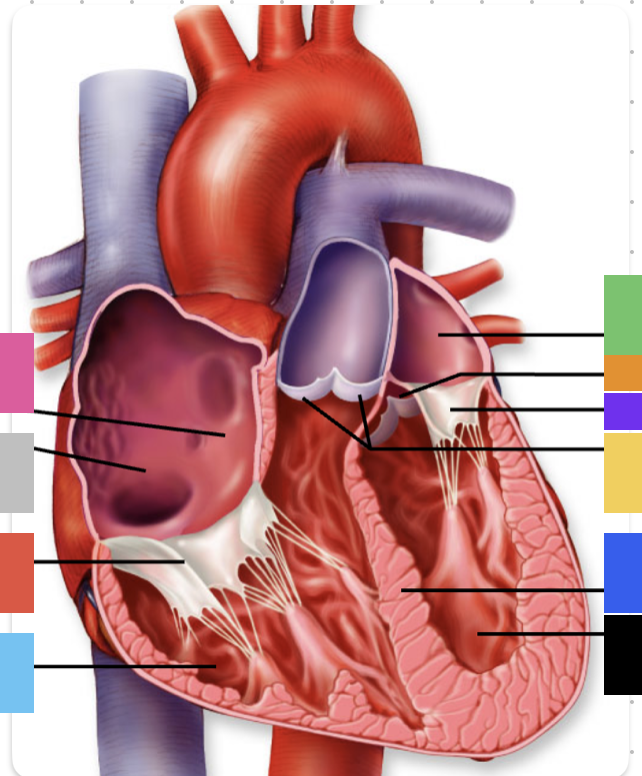

light purple

base

purple

apex

grey

right atrium

pink

right auricle

green

left atrium

green

left auricle

blue

right ventricle

orange

left ventricle

green

coronary (atrioventricular) sulcus

pink

interatrial septum

dark blue

interventricular septum

green

anterior interventricular sulcus

green

posterior interventricular sulcus

orange

aortic valve

yellow

pulmonary valve

red

tricuspid valve (right AV)

purple

bicuspid valve (left AV)

yellow

chordae tendineae

orange

papillary m.

blue

trabeculae carneae - only in ventricles

red

pectinate m. - only in R atrium

pink

fossa ovalis

grey

opening of coronary sinus

green

ligamentum arteriosum

green

fibrous pericardium

blue

parietal pericardium

pink

visceral pericardium (connective tissue) / epicardium (muscle)

purple

myocardium

grey

endocardium

pink

superior vena cava

black arrow

inferior vena cava

black

pulmonary trunk

purple

left pulmonary artery

black

left pulmonary veins

blue

(branches of) right pulmonary artery

yellow

right pulmonary veins

orange

ascending aorta

purple

aortic arch